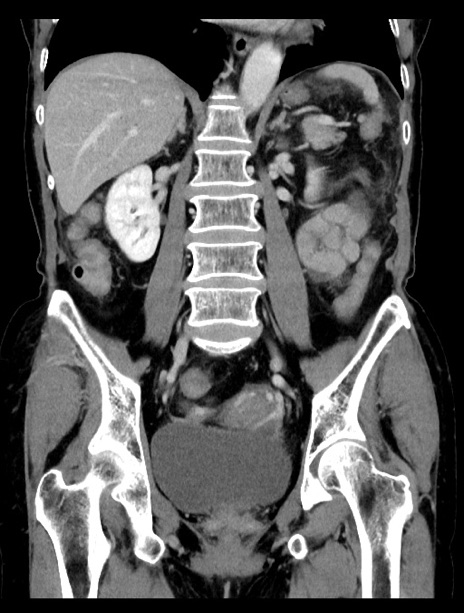

横断像

【症例】70歳代女性

【主訴】下腹部痛・嘔吐

【現病歴】2日前より腹痛あり。昨日嘔吐あり。症状改善しないため来院。

【既往歴】胃GISTに対して胃部分切除後。

【身体所見】BT 37.1℃、BP 128/77mmHg、腹部:平坦・軟、下腹部に圧痛あり。

【データ】WBC 10200、CRP 0.31